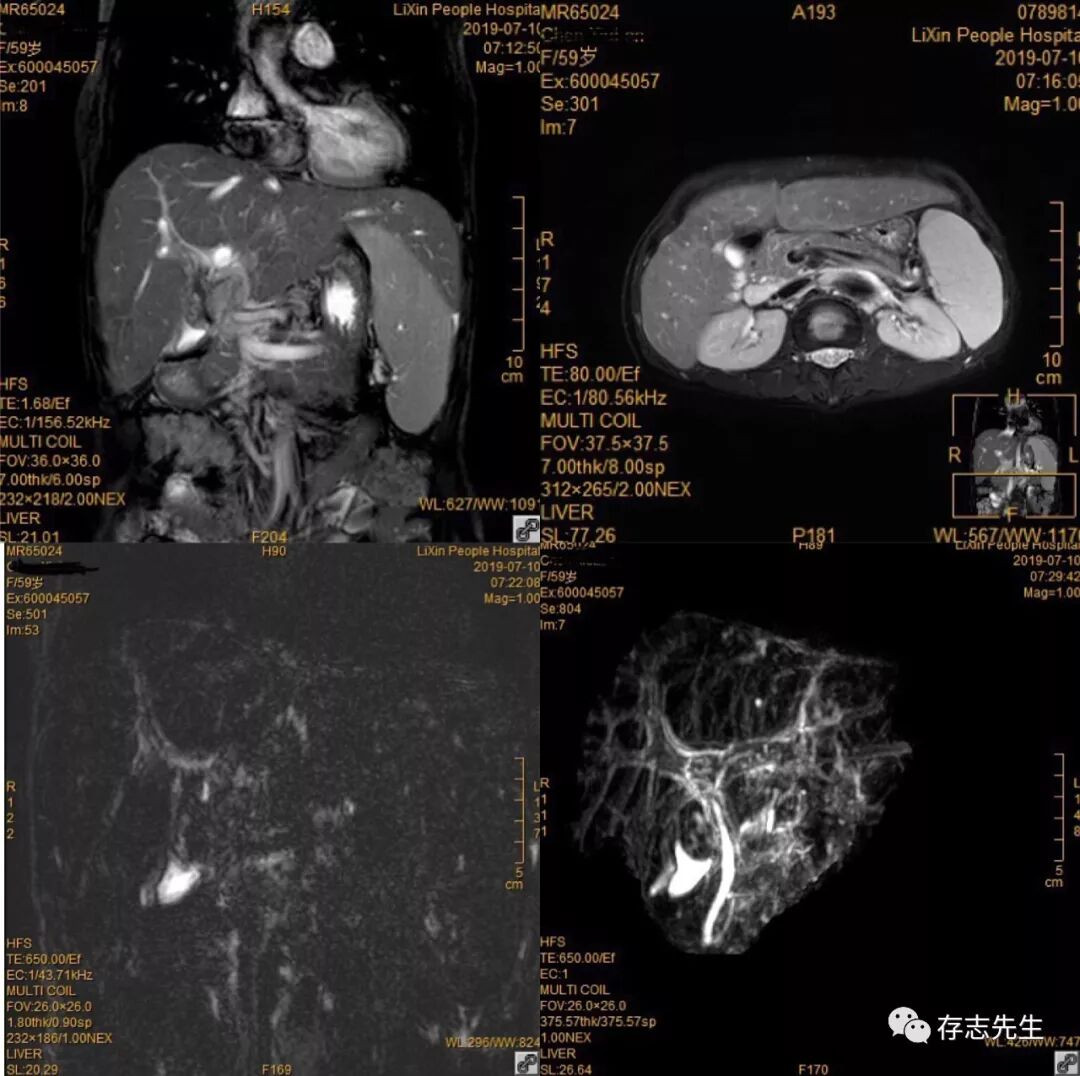

胃肠道内高信号

主任出差时同仁向我们推荐了对比剂“枸橼酸铁铵泡腾颗粒”,使用后我们做的MRCP从一定程度上改善了胃肠道带来的高信号。